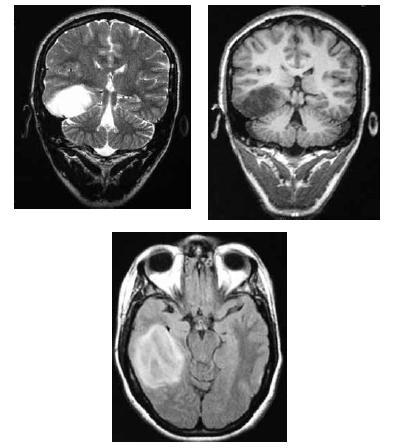

Uma mulher de 36 anos de idade foi encaminhada ao ambulatório de neurologia por dificuldade no controle das crises epilépticas. Ela referiu ter tido uma convulsão febril aos 36 meses e ter passado a ter crises em que ficava “fora do ar” aos 11 anos. Ela recebeu o diagnóstico de epilepsia generalizada do tipo ausência e foi-lhe prescrito fenobarbital. Desde então, já fez uso de primidona, ácido valpróico e diazepam, em monoterapia e associados ao fenobarbital, sem sucesso. No exame, a paciente apresentava um comprometimento da memória recente e aparentava ter um sutil deficit dos campos visuais e Babinski à esquerda. Apesar de trazer um EEG normal, foi solicitada RNM de encéfalo, que é reproduzida abaixo.